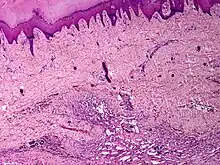

Skin angiomatosis | |

Angiomatosis is a non-neoplastic condition[1] characterised by nests of proliferating capillaries arranged in a lobular pattern, displacing adjacent muscle and fat.[2] It consists of many angiomas.[3]

It is a vascular malformation wherein blood vessels proliferate along with accompanying mature fat and fibrous tissue, lymphatics and sometimes nerves.[2] They may involve skin, subcutaneous tissue, skeletal muscle and occasionally bone.[2]